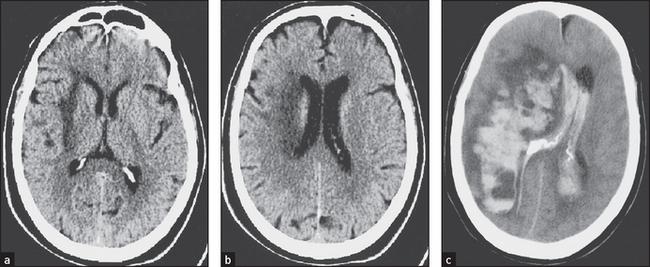

Some common examples of important diagnostic scans are shown in Figures 36.2–36.8 and 36.10.

Figure 36.2 Embolic stroke These CT scans show a large cortical infarct in the middle cerebral artery in a patient with atrial fibrillation. (Crawford. Cardiology, 3rd edn. Mosby, 2009.)

Figure 36.3 Haemorrhagic stroke These CT scans without contrast injection ((a) and (b)) show low-density changes confined to the deep subcortical regions in a patient with acute left-sided weakness. The image in (c) taken two days later shows extensive haemorrhage within the area of infarction, which has ruptured into the ventricular system. (Haaga J. CT and MRI of the whole body, 5th edn. Mosby, 2008.)